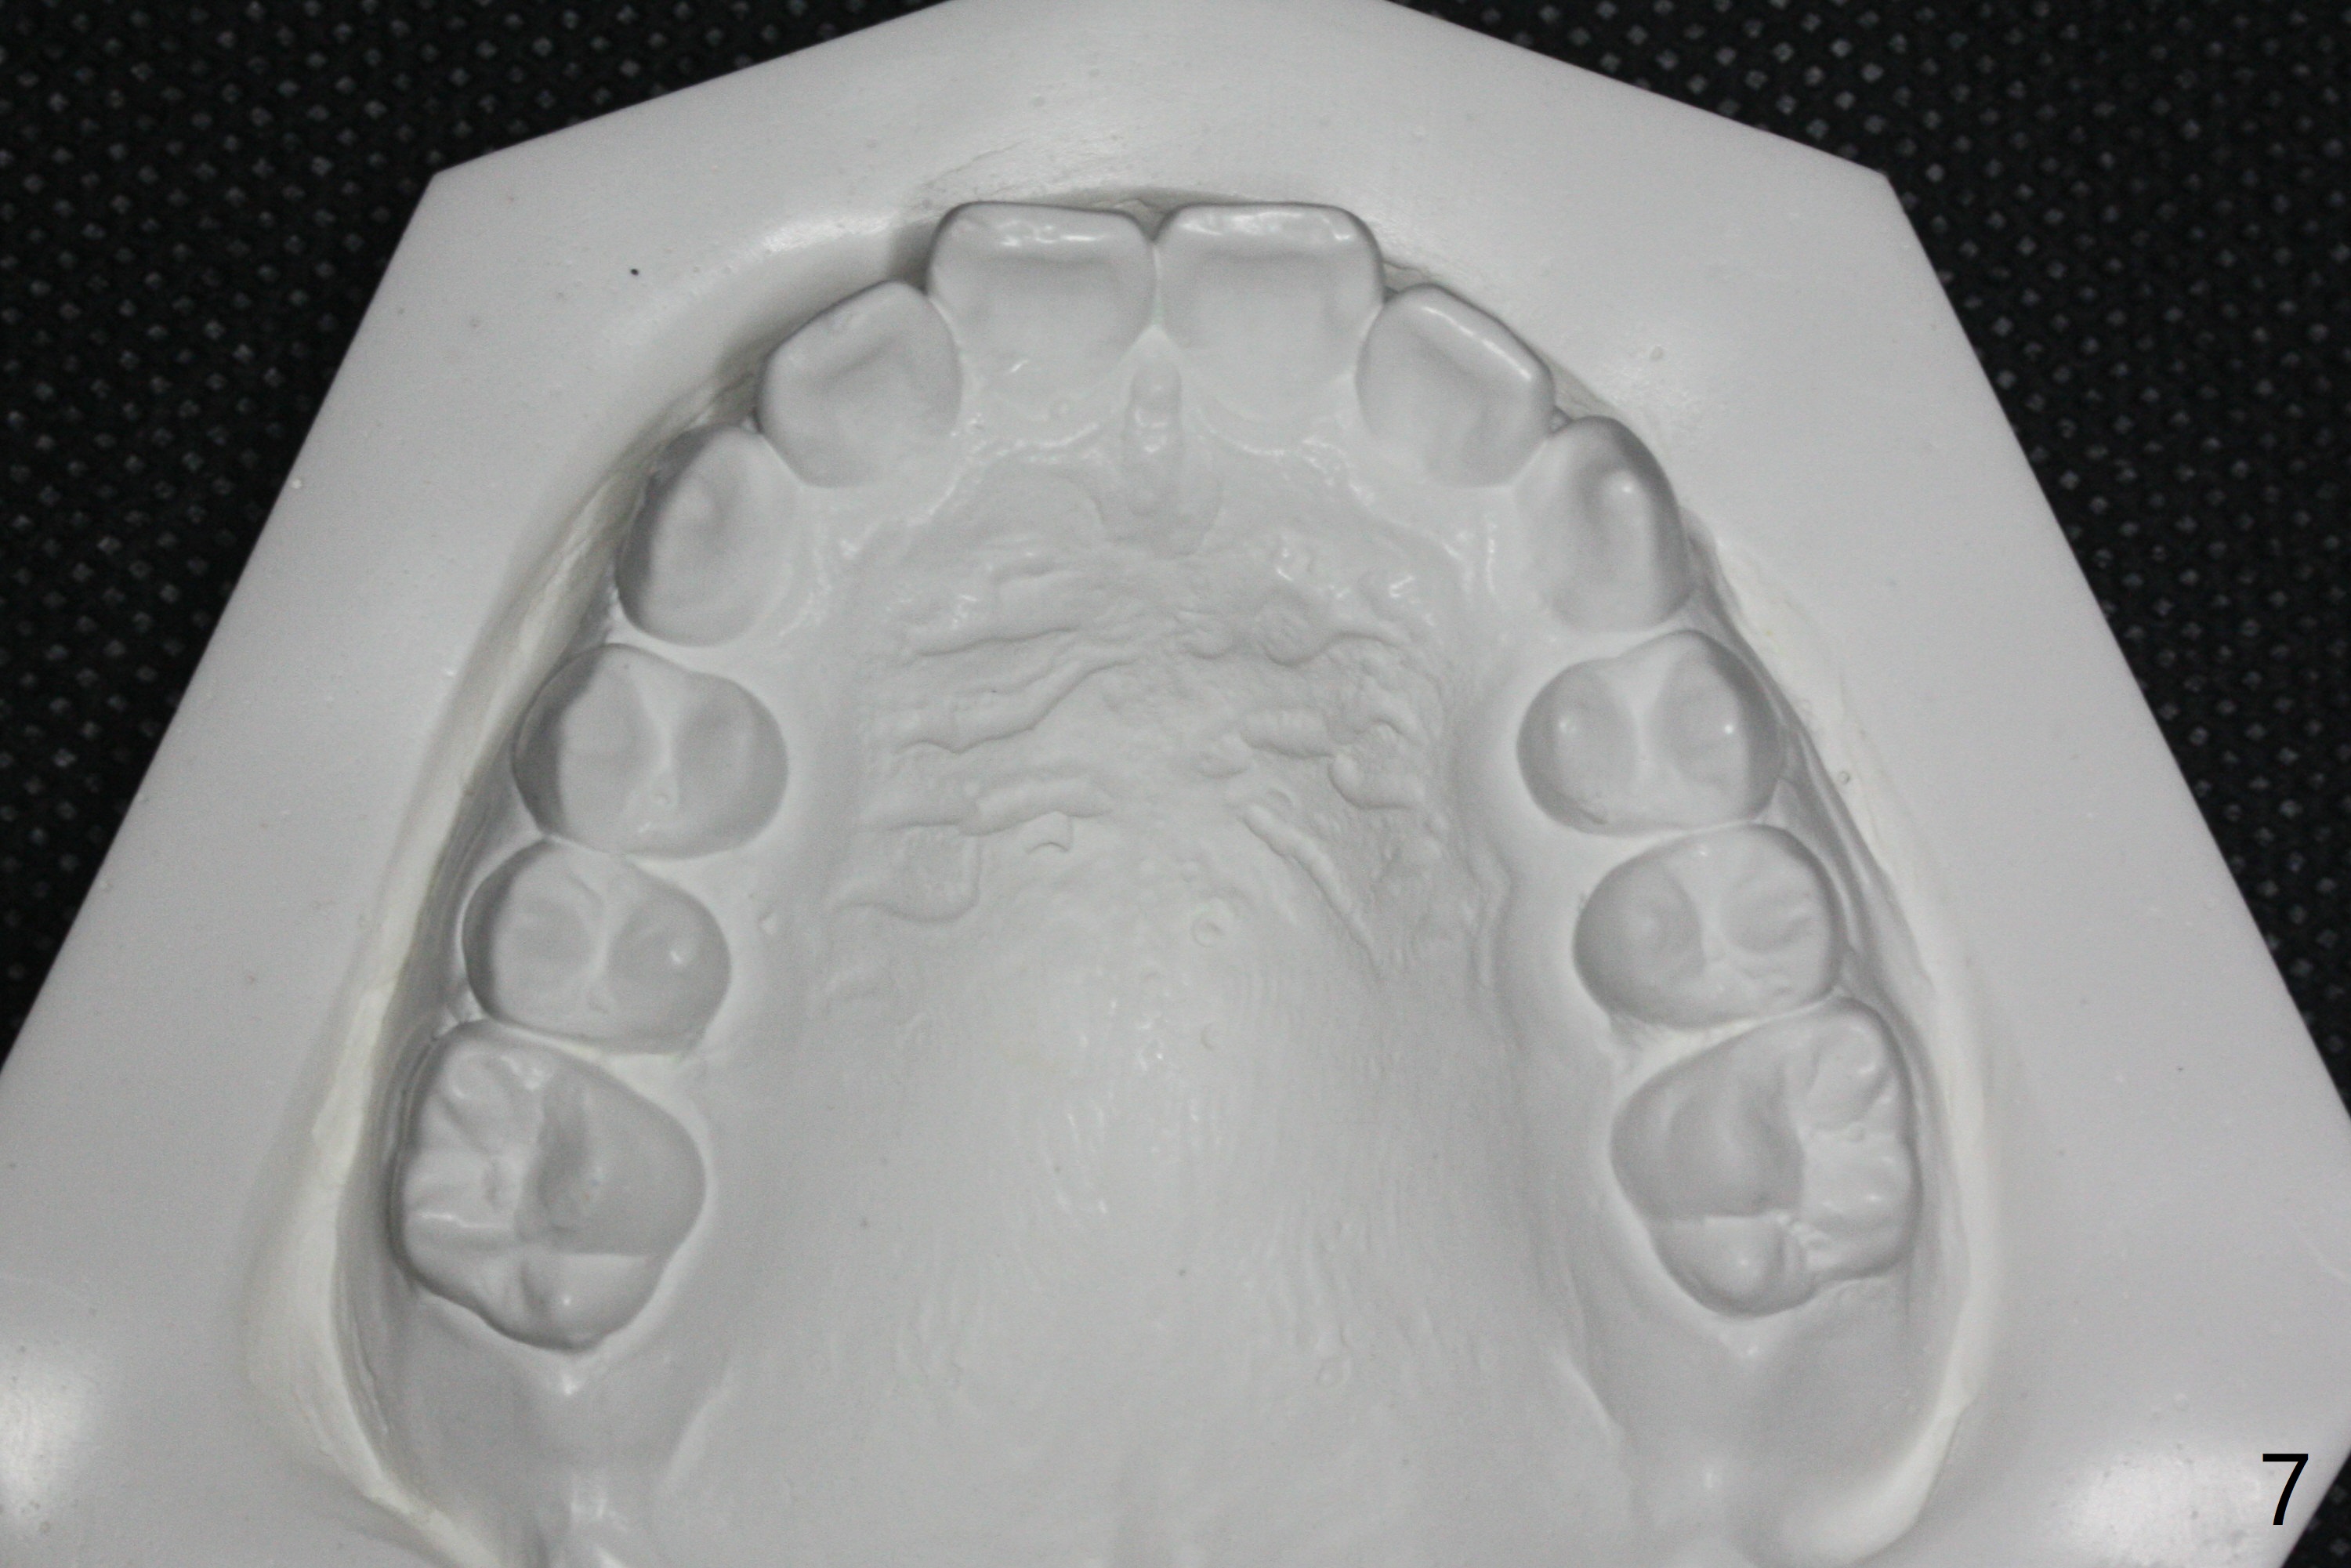

| Pre-op (11 y/o) | Post-op (12 y/o) | Follow Up (14 y/o) |

Relapse

A 11-year-old man starts orthodontic treatment and finishes in 9 months. Two years later crowding relapses because of loss of suck down retainers. It appears that lingual retainer is necessary.